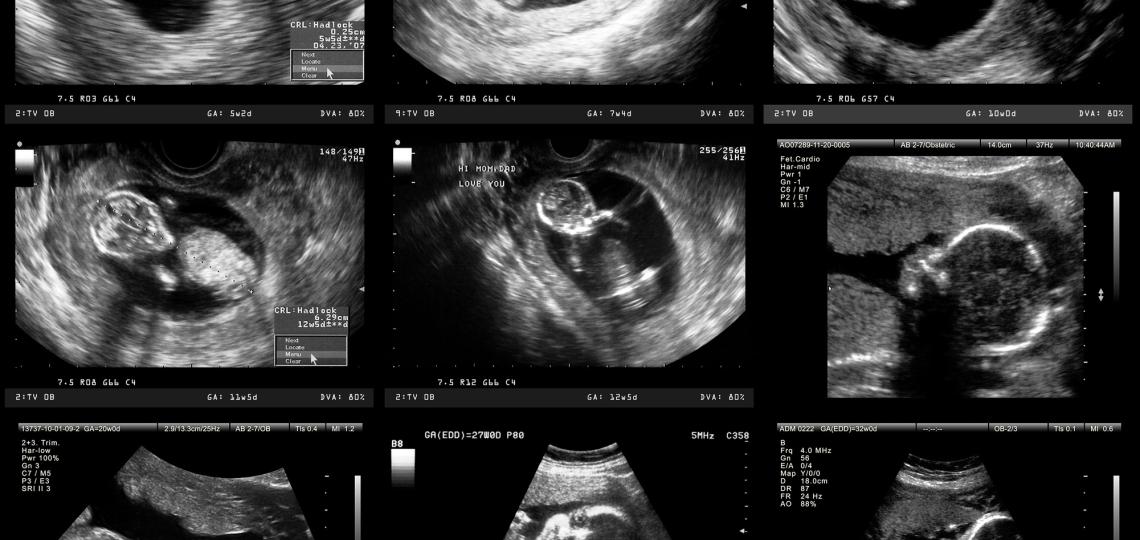

Fetal Ultrasound Course: From first trimester to advanced fetal anomalies

Join us for the upcoming three-day Fetal Ultrasound Course hosted by the Ob/Gyn maternal fetal medicine specialists/fetal surgeons at Baylor College of Medicine/Texas Children's Hospital.

In this course, attendees will learn general concepts on how to perform a fetal ultrasound examination, with live scans performed by experts in the field from Texas Children's Hospital and international institutions. There will be numerous didactic sessions focusing on different topics from general concepts to tricks and tips on how to obtain as much information as possible from the ultrasound scan. Presentations provided will be alternated with live scans and simulation practice sessions to maximize and consolidate the learning benefits offered through this course.